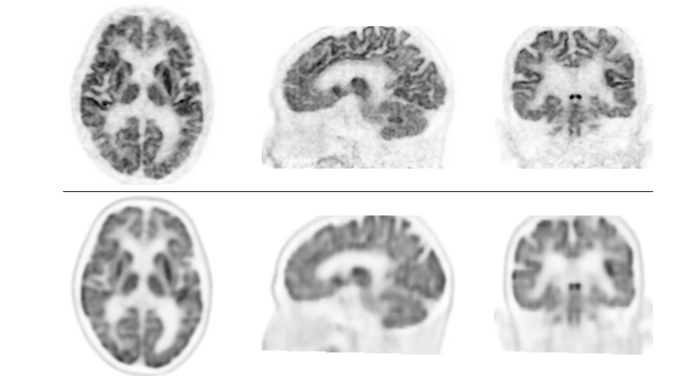

高分解能PET装置で従来よりも高画質な画像を撮像 正確な診断が可能となり、認知症の早期治療への貢献に期待

近畿大学医学部(大阪府大阪狭山市)放射線医学教室(放射線診断学部門)主任教授 石井 一成らの研究グループは、株式会社島津製作所(京都府京都市)開発の頭部・乳房を切り替えて使用できる世界初の高分解能※1 PET※2 装置「TOF※3-PET装置 BresTome」のプロトタイプを用いて、従来の装置よりも高画質(高分解能)の画像を撮像し、診断時におけるその有用性を示しました。本PET装置で撮像した高画質な画像を用いることで、正確な診断を必要とする認知症の早期治療に貢献することが期待されます。

●従来のPET/CT装置と比較し、高い分解能の良好な画像を得ることができ、臨床使用においての有用性が期待できる

PET検査は、CTやMRIのような形態の異常をみる画像検査と違い、代謝などの機能をみる機能画像検査であり、脳の分野においては、ブドウ糖代謝やアルツハイマー病の原因となる物質の蓄積を画像化することが可能です。しかし、PETのような機能画像は、形態画像と比較すると分解能が劣り、ぼやけた画像になるという欠点があります。そこで、分解能が高い、いわゆる解像度の高い画像を撮像できるPET装置の開発が望まれています。

臨床研究では、主に認知症患者に対し、ブドウ糖代謝とアミロイド※4沈着の有無をみる検査を行い、本PET装置と従来のPET/CT装置で撮像した画像を比較検討しました。その結果、全例において本PET装置で撮像した画像の分解能が優れていることが明らかとなり、症例によっては診断が変わることさえありました。これにより、臨床使用においても、本PET装置が正確な診断を可能にし、認知症の早期治療に貢献するものであることが示されました。

検証では、認知機能障害、てんかん等の18名の患者において、脳FDG-PET装置を用いて撮像した画像と、本PET装置で撮像した画像を比較しました。次に、認知機能障害患者17名において、従来のPET/CT装置を用いた画像と本PET装置で撮像した画像を比較しました。その結果、全例において本PET装置による画像の分解能が優れており、従来型よりも分解能が高く、細かいところまで描出できることが示されました。